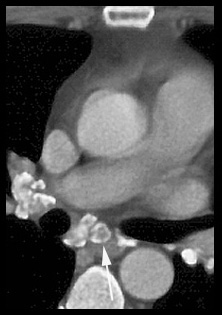

CT: Egg shell calcification of lymph nodes